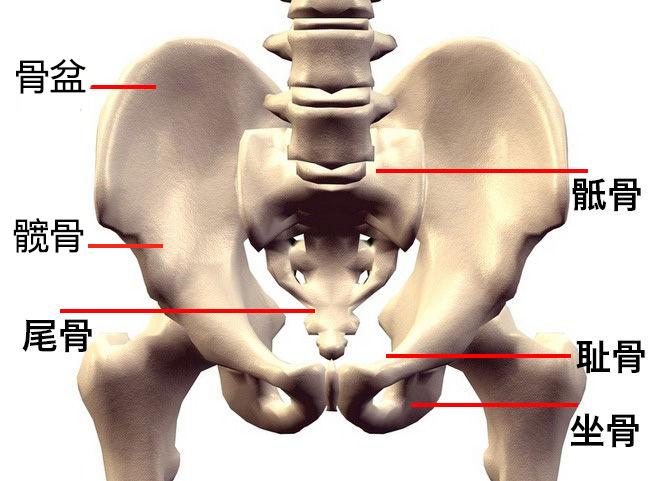

骶(di)骨:从背后沿着脊椎一直往下摸,腰部以下微微凸起的地方是骶骨

腰部两边骨头突出图片

腰部骨头图

腰部骨头结构

腰部骨骼结构图

腰部骨头名称分布图